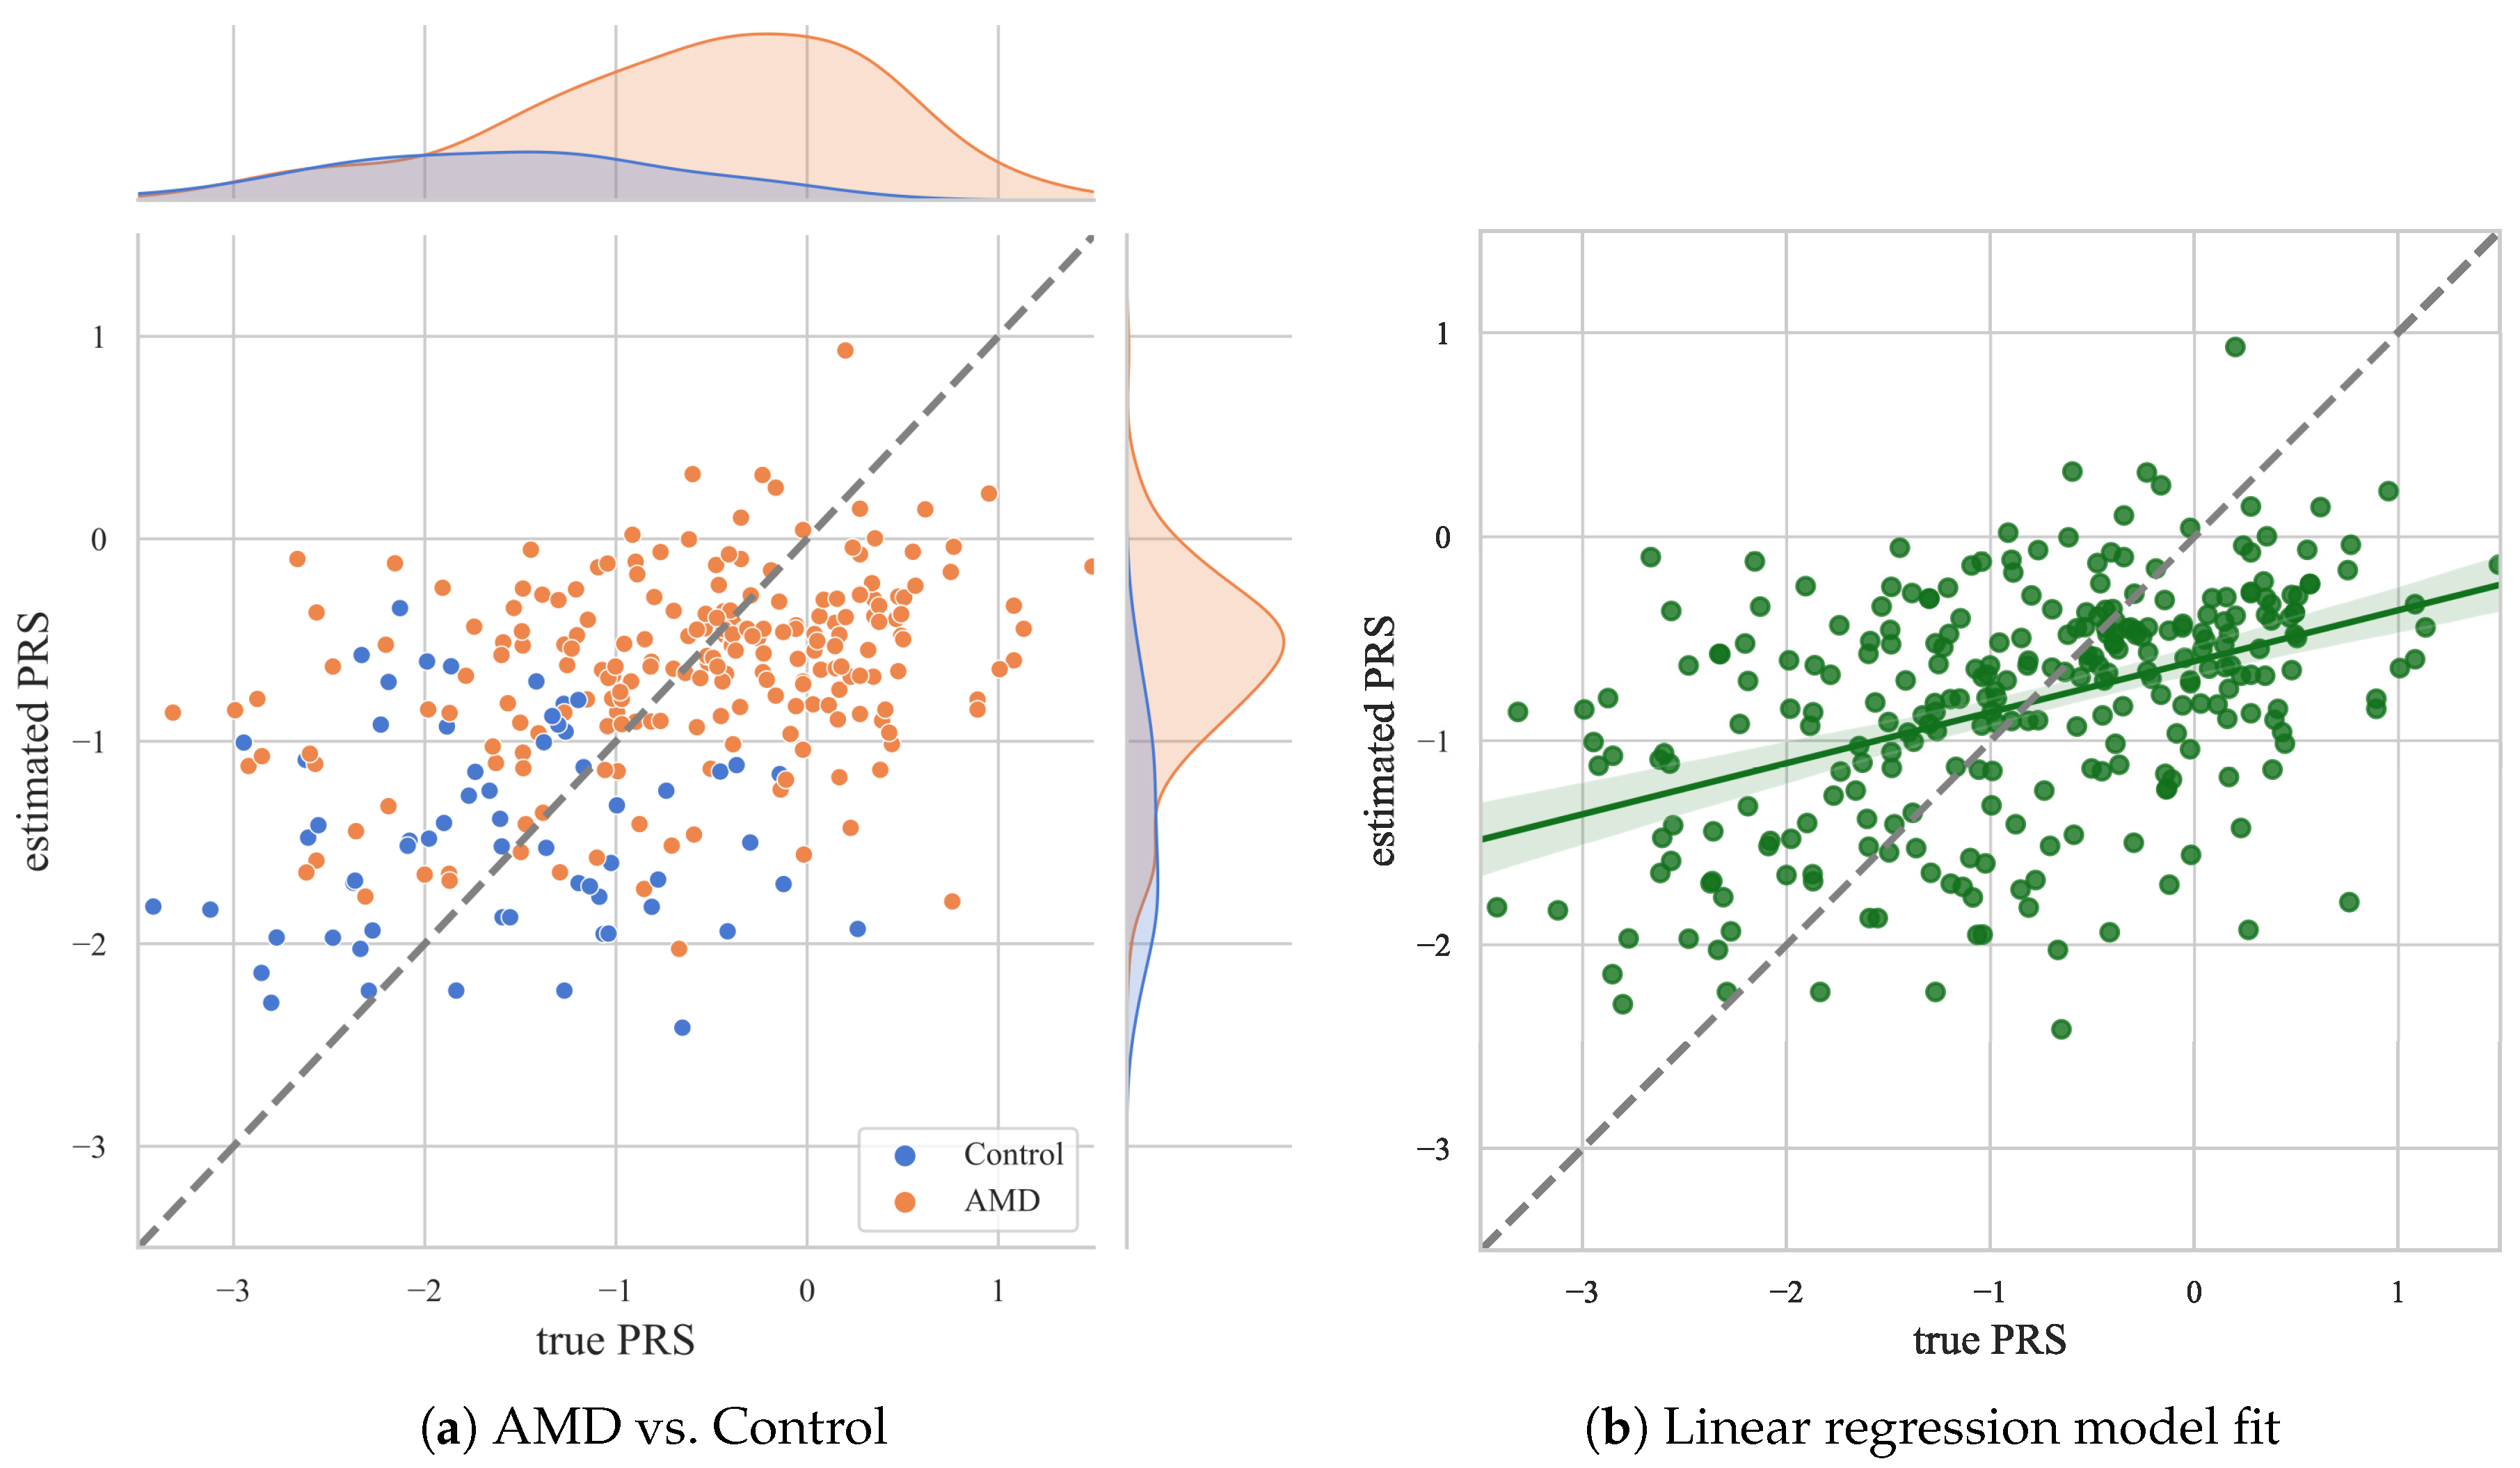

3. Results

4. Discussion